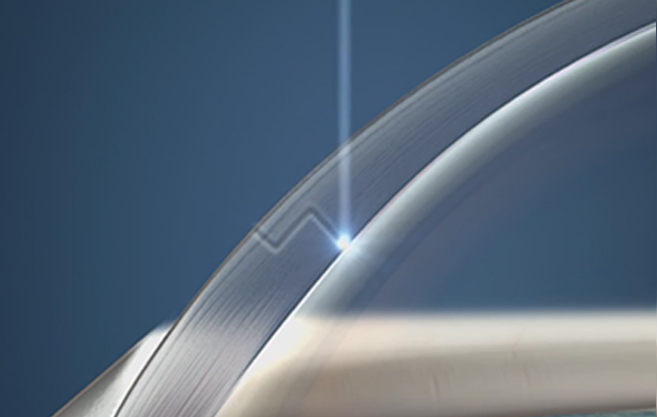

수정체 전낭 절개시 완벽한 원이

완벽한 시력 결과를 낳습니다.

정확하고 매끄러운

레이저 절개